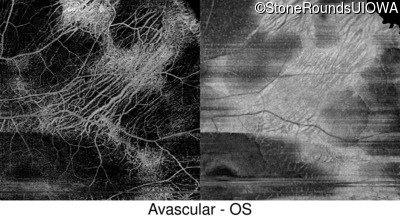

Swept-Source OCT - Left - 20/16 -2

Exemplar